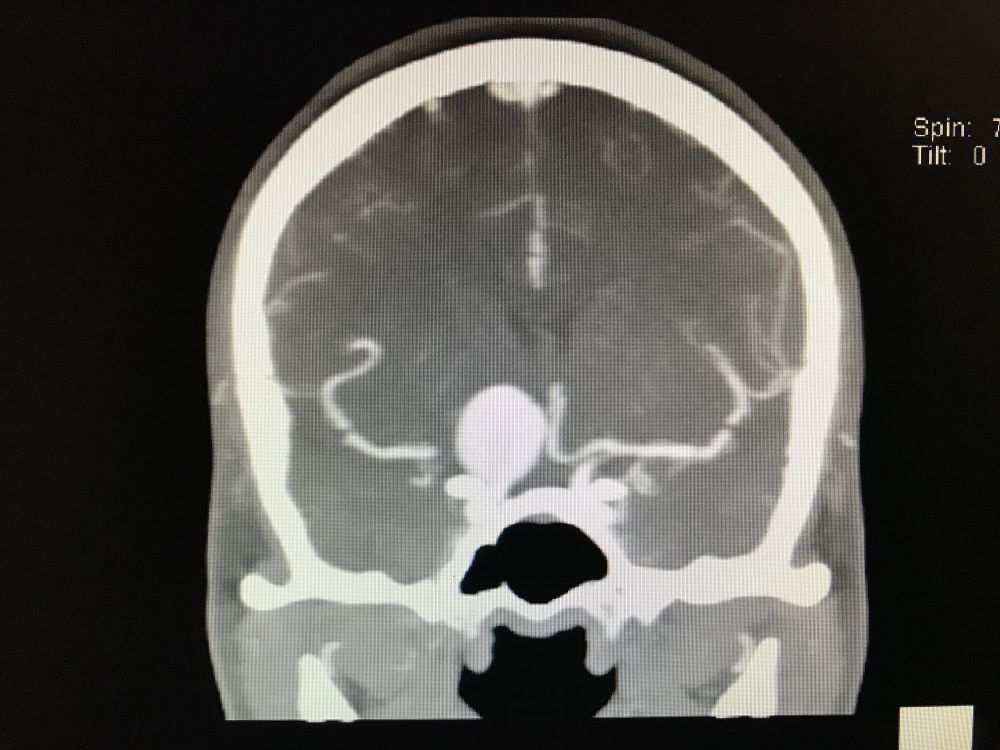

术后复查CT